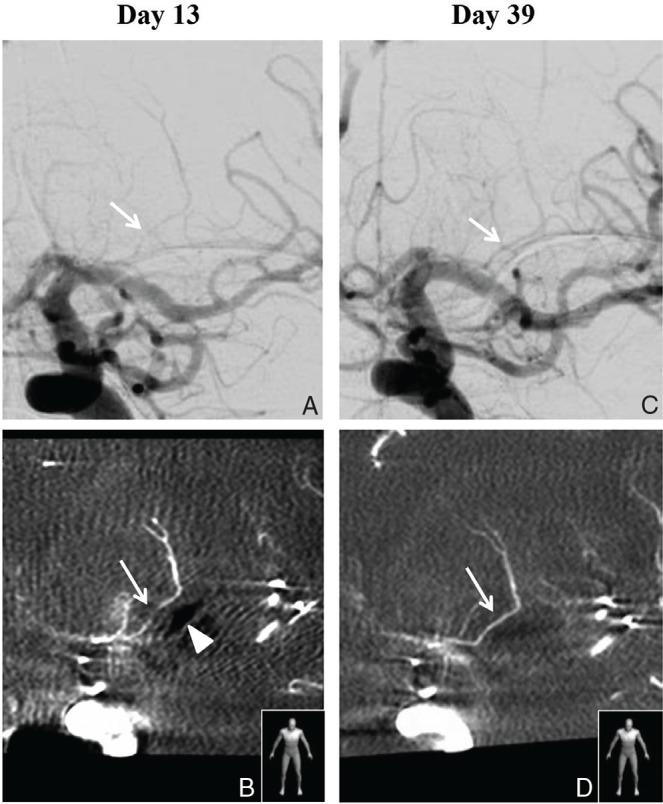

Implantation of carmustine-impregnated wafers (Gliadel) into the tumor resection cavity has demonstrated a survival benefit for patients with malignant glioma. However, some precautions should be taken regarding Gliadel implantation. We report a case of a 63-year-old man with glioblastoma who was implanted with Gliadel after a left temporal lobe tumor had been removed, and who later developed vasospasm of the lenticulostriate artery close to the implanted Gliadel, leading to serious cerebral infarction. Therefore, the implantation of Gliadel in cases where important vessels run close to the resection cavity should be considered with great caution.